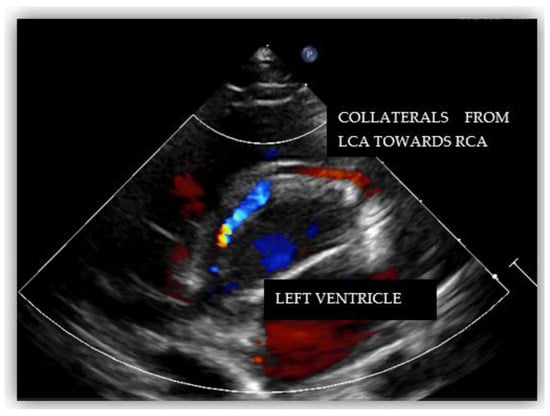

2. Case Report #1